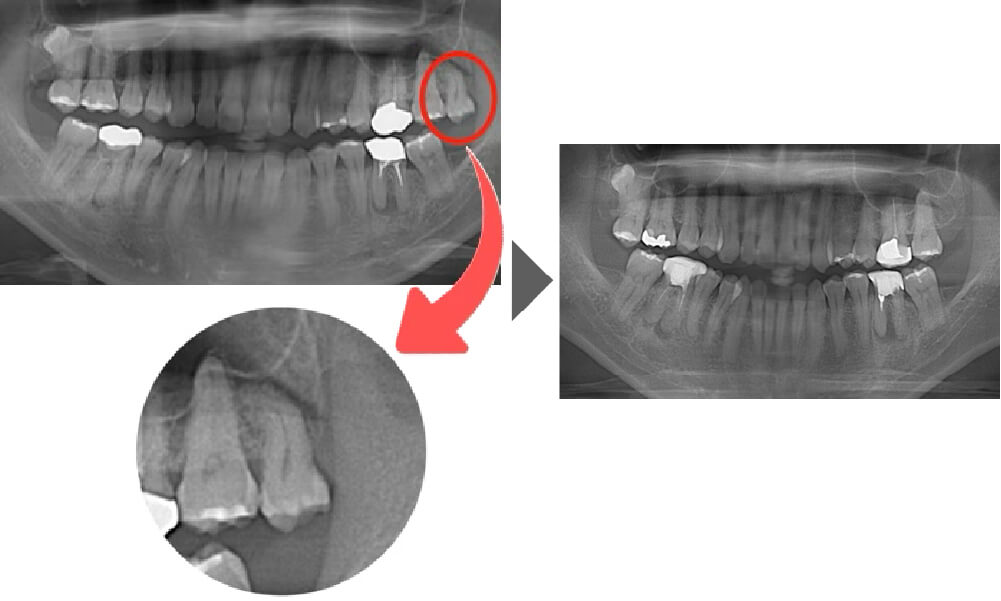

抜歯症例①

ご覧いただいた通り、歯根の先が隣の歯と比べても湾曲しています。 通常よりも抜歯の難易度が上がる症例です。

【抜歯所要予約時間】

15分

(麻酔の時間があるので処置自体はもっと短いです)